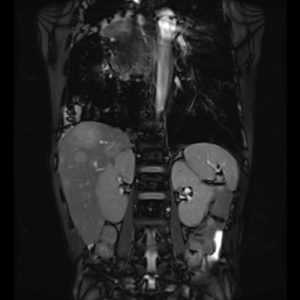

Chẩn đoán toàn thân: đầu, cổ, cột sống, khớp, bụng, tiểu khung, mạch máu